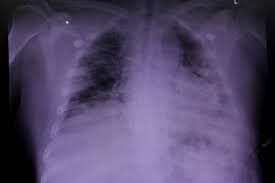

নিজস্ব প্রতিনিধি , কলকাতা - ফুসফুসে বেড়েই চলেছে ক্যান্সারের প্রকোপ। অনেকের মতে , শুধু ধূমপান থেকেই হয়তো বাড়ছে ক্যান্সার। কিন্তু চিকিৎসকদের মতে, ধূমপান না করলেও দূষণ, রেডন গ্যাস, দীর্ঘদিনের ফুসফুসের সংক্রমণের মতো কারণ থেকেও ফুসফুসে ক্যান্সার হতে পারে।

ক্যান্সারের প্রাথমিক উপশমগুলি অনেকেই সাধারণ সর্দি কাশি ভেবে এড়িয়ে চলে। কিছু বিশেষ লক্ষণ যেমন দীর্ঘদিনের কাশি, মাঝে মাঝেই শ্বাসকষ্ট , কফের সঙ্গে রক্ত, হটাৎ বুক পিঠে ব্যথা, গলার স্বর বসে যাওয়া, ওষুধ খেয়েও কোনো পরিবর্তন না হওয়া, হঠাৎ ওজন কমে যাওয়া কোন কারণ ছাড়াই - এগুলো হতে পারে ক্যান্সারের লক্ষণ।

বিশেষজ্ঞরা জানান ," এই উপসর্গগুলো বারবার দেখা দিলে অবহেলা করা বিপজ্জনক। বিশেষত ধূমপান করেন, এমন ক্ষেত্রে ঝুঁকি আরও বেশি। রোগ প্রাথমিক অবস্থায় ধরা পড়লে চিকিৎসা সহজ হয় এবং সেরে ওঠার সম্ভাবনাও বেড়ে যায়। তাই উপসর্গ দীর্ঘদিন ধরে থাকলে, বা দৈনন্দিন কাজে শ্বাসকষ্ট বাড়তে থাকলে দ্রুত ফুসফুস বিশেষজ্ঞের পরামর্শ নেওয়া জরুরি ।"